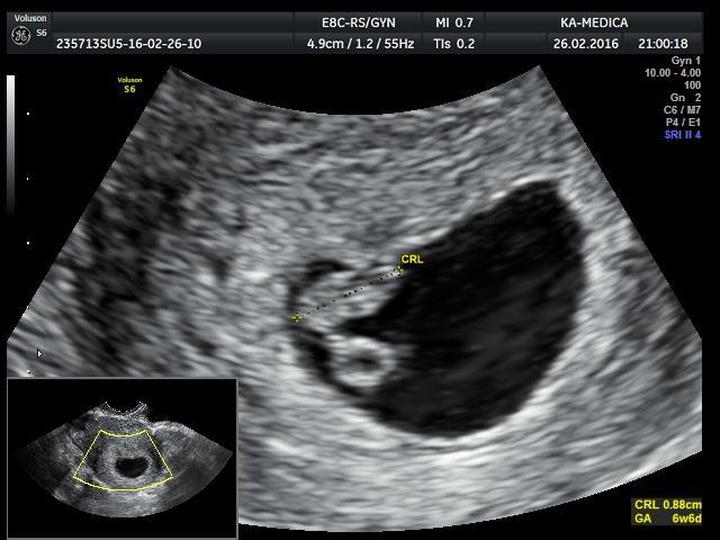

| USG | Możliwość usłyszenia bicia serca maluszka |

Na koniec należy podkreślić, że każda ciąża to niepowtarzalna historia. Przyszłe mamy muszą pamiętać, że nie wszystkie wymienione objawy muszą wystąpić. Niektóre kobiety przechodzą ten czas bez większych zawirowań, podczas gdy inne czują się jak prawdziwe mamy od momentu spełnienia marzeń o macierzyństwie. Ważne jest, aby dbać o siebie, słuchać swojego ciała i pamiętać o regularnych wizytach u lekarza, tak aby z niecierpliwością oczekiwać na pierwsze USG i podziwiać bijące serce swojego maluszka!